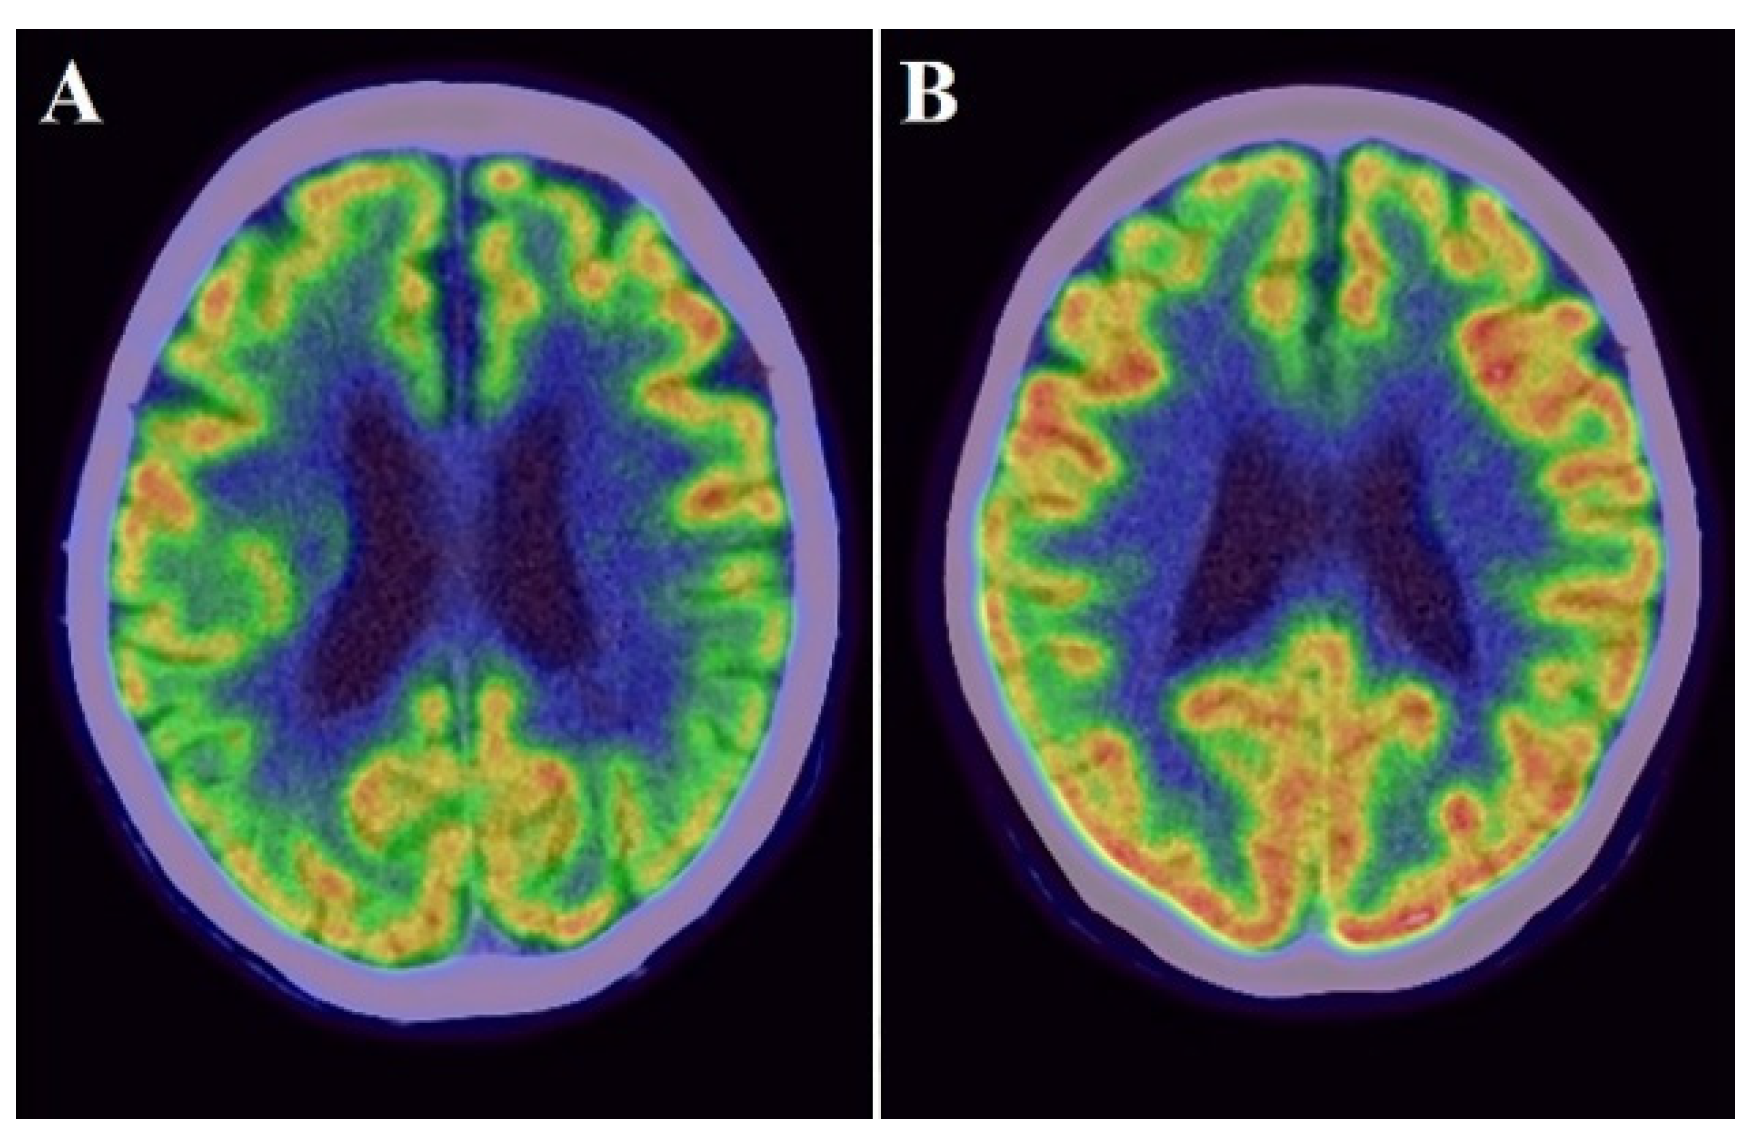

Figure 2.

Examples images of an individual with lower PiB uptake ((A): cortical SUVR value = 0.804) and with higher PiB uptake ((B): cortical SUVR value = 2.584).